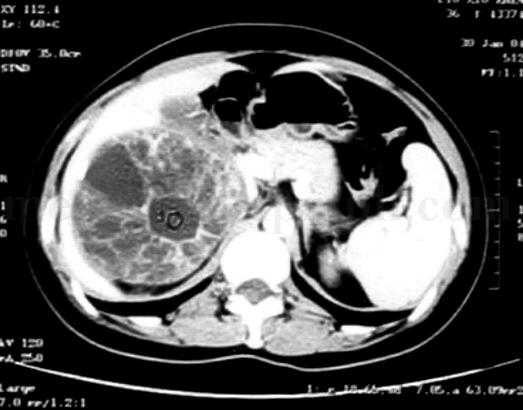

CT:右肾上极囊实性肿物,9cm×10cm×10cm,内部密度不均匀,似由多个囊性成分组成,增强显示肿瘤实性部分及分隔强化,囊性成分未见明显强化。盆腔和后腹膜未见肿大淋巴结,余未见异常(图1)。

图1 CT